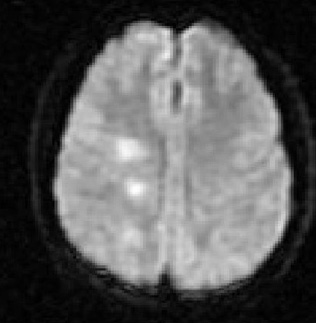

Séries de imagens de RNM do cérebro de um paciente com encefalomielite disseminada aguda: imagens ponderadas por difusão do mesmo paciente mostram sinal de alta intensidade na mesma área, o que está correlacionado à difusão aumentada (intensa nos mapas de coeficiente de difusão aparente [CDA])

Do acervo pessoal de Catalina C. Ionita, MD; usado com permissão

Veja esta imagem em contexto nas seguintes seções: